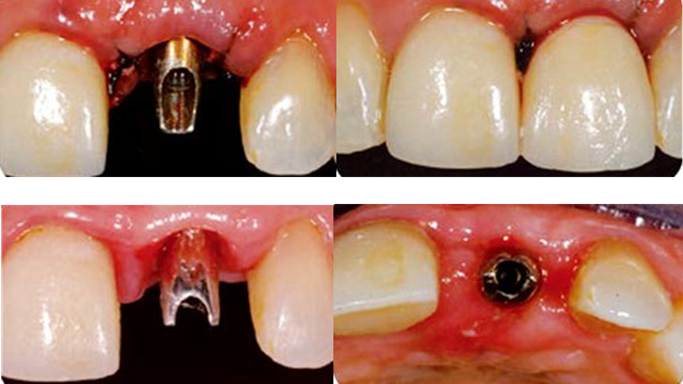

Clinical case: Replacement of fractured central incisor (#11) with immediate implant

& Root Membrane Technique

- Courtesy of Dr. Miltiadis Mitsias, Greece -

AnyRidge, Root Membrane Technique, retrospective study, long-term study, immediate implants, bone resorption, bone preservation, Dr. Miltiadis Mitsias,survival, success, maxillary anterior, single replacement

AnyRidge implant system, Root Membrane kit

“AnyRidge with Root Membrane Technique shows

comparable long-term success rates to

conventional immediate implants. ”